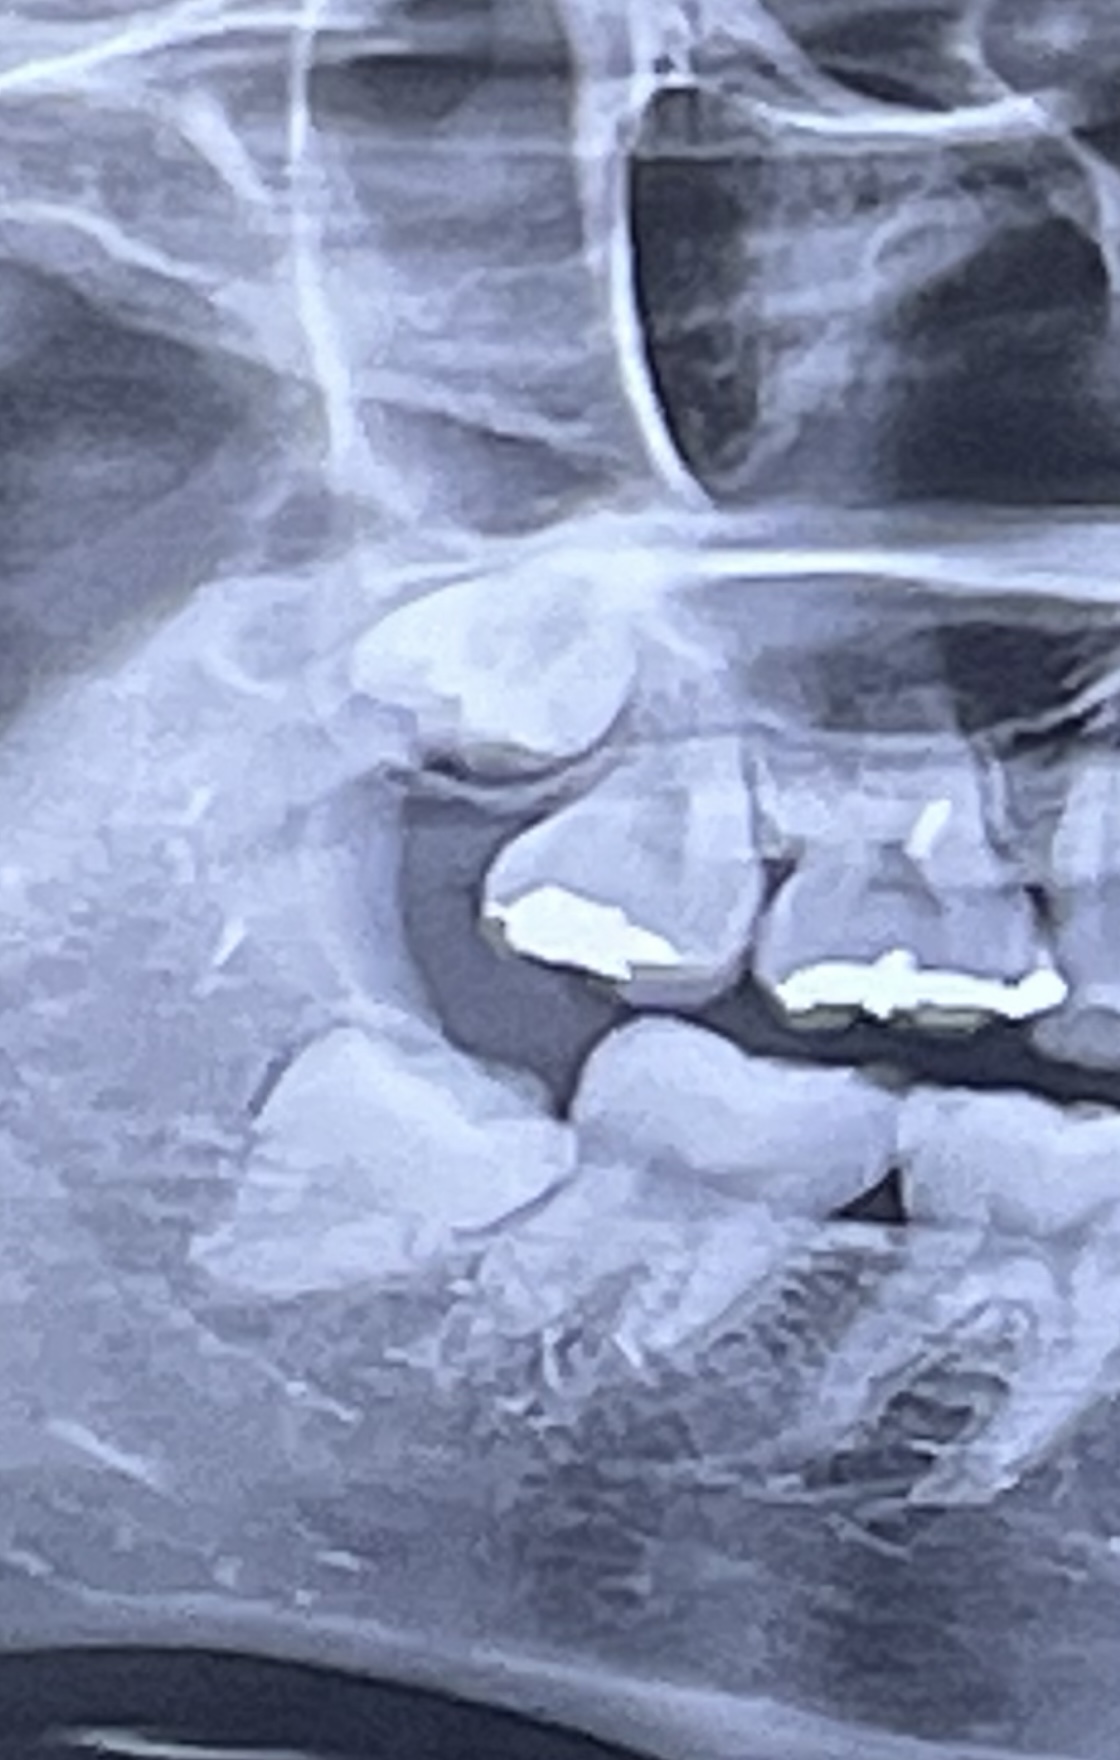

다른 치과를 가봐서 사진찍었는데 성장기쯤에 아랫 사랑니를 뺏어야 했다고 하더라고 처음들어보는말인데

아래사랑니가 치아를 양쪽으로 눌러서 아랫니가 균형이안맞아

윗니도 나오는거라하더라고